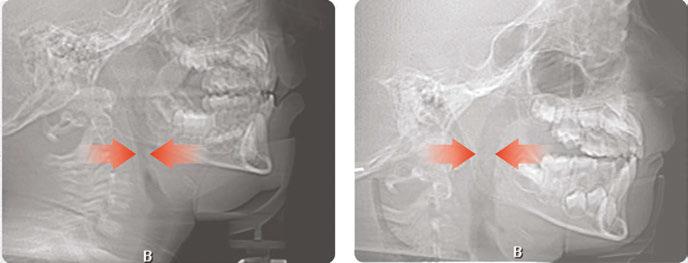

Over 10 years ago, we began Orthotropic® treatment for a 5 year, 3-month-old boy with a diagnosis of Pierre-Robin Sequence, Obstructive Sleep Apnea (OSA), and Failure to Thrive (Figure 1). With lack of forward development of the face com-

monly seen in Pierre-Robin patients, his airway was compromised, resulting in OSA. The Failure to Thrive diagnosis likely resulted from insufficient growth hormone being released during the deeper stages of sleep. This treatment began before any permanent teeth erupted. Our goal was to eliminate OSA.

Orthotropics® uses removable appliances to laterally expand the upper arch while simultaneously advancing the upper anterior teeth to their proper place in the face. Then the mandible is developed forward. Orthotropics® is my preferred treatment in cases like this because it negates the head gear-effect producing better facial balance5 and also can result in substantial airway improvements (Figure 2).6

This young boy had great parental support and was very compliant during the treatment. A posttreatment sleep test showed no signs of sleep apnea.7 Failure to Thrive was also overcome. Now at 17 years old, this patient is 5 ft. 7in. tall and is still growing. I believe that improved breathing and sleep has resulted in an increase in HGH production which allowed him to resume normal growth. He’s an aggressive tennis player with a big smile and no return of his OSA (Figure 3). Thankfully, he’s an excellent student with no evidence of brain damage from his early OSA diagnosis.

Figure 1: Pretreatment gallery Figure 3: Today, he’s a tennis player Figure 2: Pre- and posttreatment airways